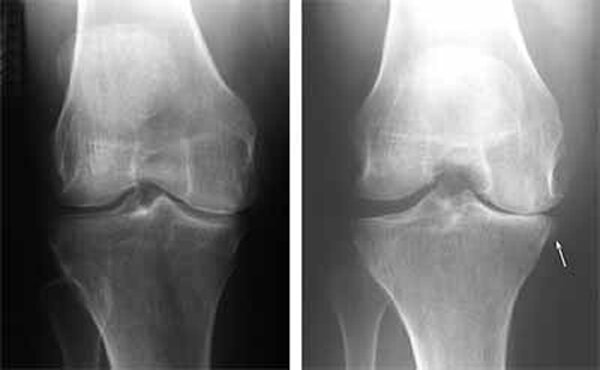

مفصل زانو

دکتر محسن مردانی فوق تخصص ارتوپدی و پزشک هیات پزشکی ورزشی گیلان گفت: می دانید که در سنین بالا ساییدگی مفصلی و ارتروز در بین زنان شایعتر از مردان است ولی علت آن تا کنون به درستی شناخته شده نبوده است. اینک مطالعه ای جدید آن را به تفاوت در مواد درون مایع مفصلی ارتباط داده است